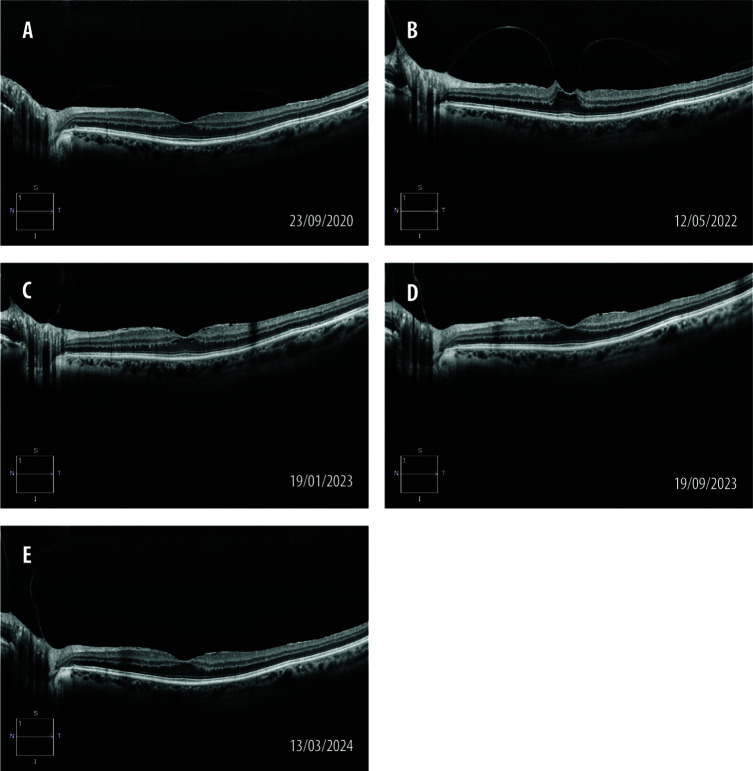

本病例报告探讨0.5%吲哚美辛滴眼液(Indo0.5)预防视网膜前膜牵拉进展的潜力。一例72岁的进行性玻璃体黄斑牵引患者采用Indo0.5治疗,8个月内视网膜内囊肿明显减少,16个月后完全吸收,22个月后视网膜轮廓完全恢复。一项小型文献综述强调了吲哚美辛对影响前段的各种疾病的抗炎作用,并表明0.5%浓度的吲哚美辛也可能有效地治疗视网膜炎症。Indo0.5可能是减缓视网膜前膜牵引进展的非侵入性选择,支持进一步研究以优化治疗策略。

This case report explores the potential of 0.5% indomethacin eye drops (Indo0.5) in preventing the progression of epiretinal membrane traction. A 72-year-old patient with progressive vitreomacular traction was treated with Indo0.5, leading to a significant decrease in intraretinal cyst within 8 months, complete resorption after 16 months and full restoration of the retinal profile after 22 months. A mini literature review highlights the anti-inflammatory effects of indomethacin for various conditions affecting the anterior segment and suggests that the 0.5% concentration may also be effective in managing retinal inflammation. Indo0.5 could be a non-invasive option for slowing epiretinal membrane traction progression, supporting further research to optimize treatment strategies.